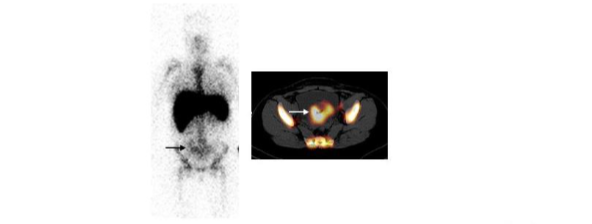

Although CT is the imaging test of choice in the diagnostic workup of intraabdominal infections, WBC imaging has an important, adjunctive role in the workup of these infections. The test is sensitive and specific for intraabdominal infections such as abscesses and urinary tract infections²²–²⁴. In one investigation, both positive and negative results provided useful information for patient management²⁵. Furthermore labeled leukocytes do not accumulate in normally healing incisions or in uninfected tumors, which are important advantages over both ⁶⁷Ga and ¹⁸F-FDG (Figure 9)¹⁰.

Figure 9.

Endometritis. On the anterior indium-111 labeled leukocyte image (left) there is faintly increased labeled leukocyte activity in the pelvis (arrow). On the axial SPECT/CT image (right) there is increased activity throughout much of the uterus (arrow). An infected uterus with abscess formation was removed at surgery. The patient had undergone Caesarean section two weeks previously. CT scan (not shown) was inconclusive.